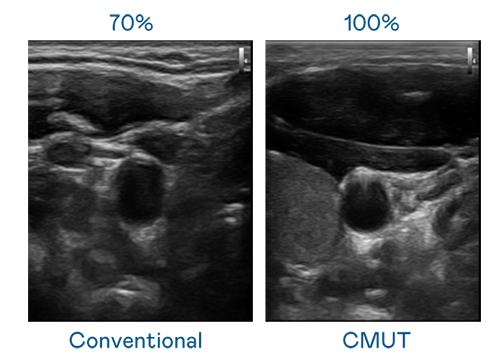

CMUT 技术是一种用电容式微机电元件来产生超音波讯号的技术。与传统 PZT 压电式技术相比,CMUT 频宽增加 30%,更宽频的超音波讯号让影像解析度大幅提升,是实现高影像品质医疗超音波扫描、促进精准医疗发展的关键技术。

大频宽带来超清晰影像

超音波影像的解析度高低,首先取决于探头能发出的讯号频宽。771771威尼斯cm CMUT 可提供高清晰的超音波讯号,提供高频宽、高灵敏度、影像纹理细节更高的超音波影像,协助医护人员缩短影像判读时间及利用精准的医疗影像进行诊断。